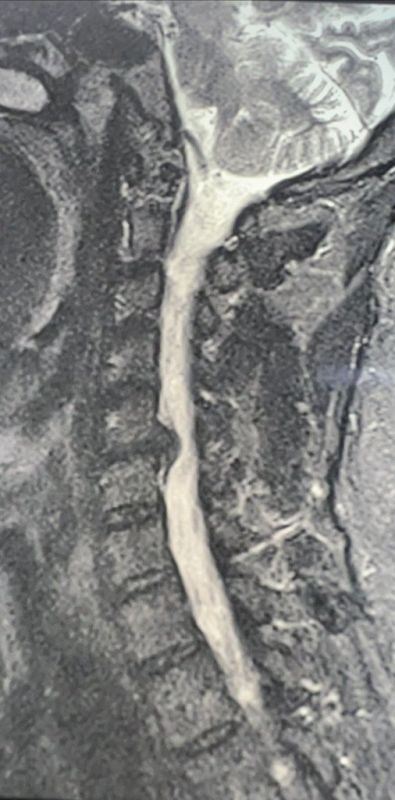

Нейрохирурги Воронежской городской клинической больницы №11 спасли руку 49-летнему мужчине с грыжей. В конце октября в нейрохирургическое отделение стационара Воронежской городской больницы №11 поступил 49-летний мужчина. В течение месяца его мучали...